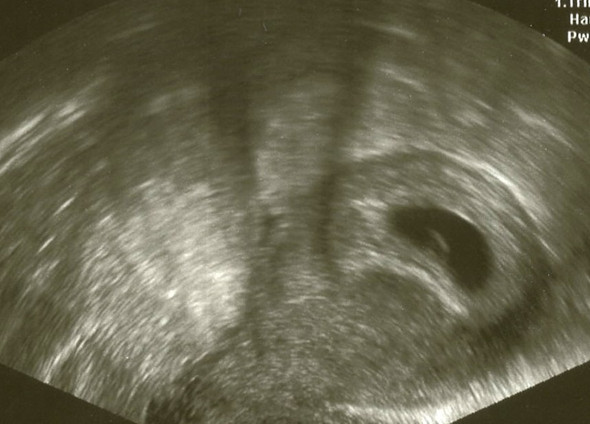

Die Fruchthöhle ist schwarz und deutlich auf dem Ultraschall zu sehen Da durch einen Ultraschall in der 3 Schwangerschaftswoche kein Ergebnis zu sehen ist und die meisten werdenden Mütter noch nichts von einer möglichen Schwangerschaft ahnen, wissen sie es aber ab der 4 SSW, wenn die cm 6'44 cm In der 6. Hier ist der Dottersack nun sehr deutlich zu sehen (man sieht hier auch, wie wichtig die Qualität der Ultraschallgeräts sein kann Der Dottersack wurde hier vermessen und hat einen Durchmesser von 3 Millimetern Der Embryo ist auf diesem Bild noch nicht davon abgrenzbar Ultraschallbild 56 SSW Ein Ultraschallbild vom 6 der 6. Deine vermeidlich 6SSW Ultraschalluntersuchung kann sich also als ein Flopp herausstellen, da man auf dem Ultraschall noch gar nichts sieht Es kann nämlich sein, dass du erst in der 5Schwangerschaftswoche bist, da dein Eisprung erst ein oder zwei e später war oder die Einnistung der befruchteten Eizelle an deiner Gebärmutterwand erst.